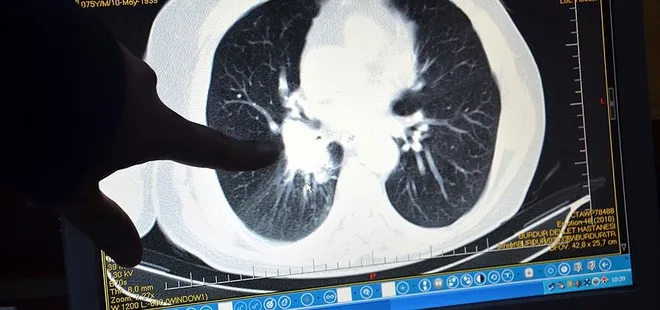

Akciğer kanseri, tüm kanser türleri arasında en yüksek ölüme yol açan hastalık olarak dikkat çekiyor. Göğüs Cerrahisi Uzmanı Opr. Dr. Volkan Yılmaz, akciğer kanseri hakkında bilgilendirmelerde bulundu.

Akciğer kanserine yakalanan hastaların çoğunun tanı anında semptomatik olduğunu belirten Opr. Dr. Yılmaz, "Sıklıkla öksürük, nefes darlığı, hemoptizi (kanlı balgam) ve göğüs ağrısı gibi spesifik belirtilerle başvuran hastalarda; halsizlik, kilo kaybı ve ateş gibi non-spesifik şikayetler de görülebilmektedir. Uzmanlar, akciğer kanserinin erken teşhis edilmesinin tedavi başarısını önemli ölçüde artırdığını vurguluyor. Son yıllarda tanı ve tedavi tekniklerinde yaşanan gelişmeler, minimal invaziv yöntemler ve hedefe yönelik tedaviler, bu kanser türüyle mücadelede önemli bir fark oluşturmaktadır" dedi.